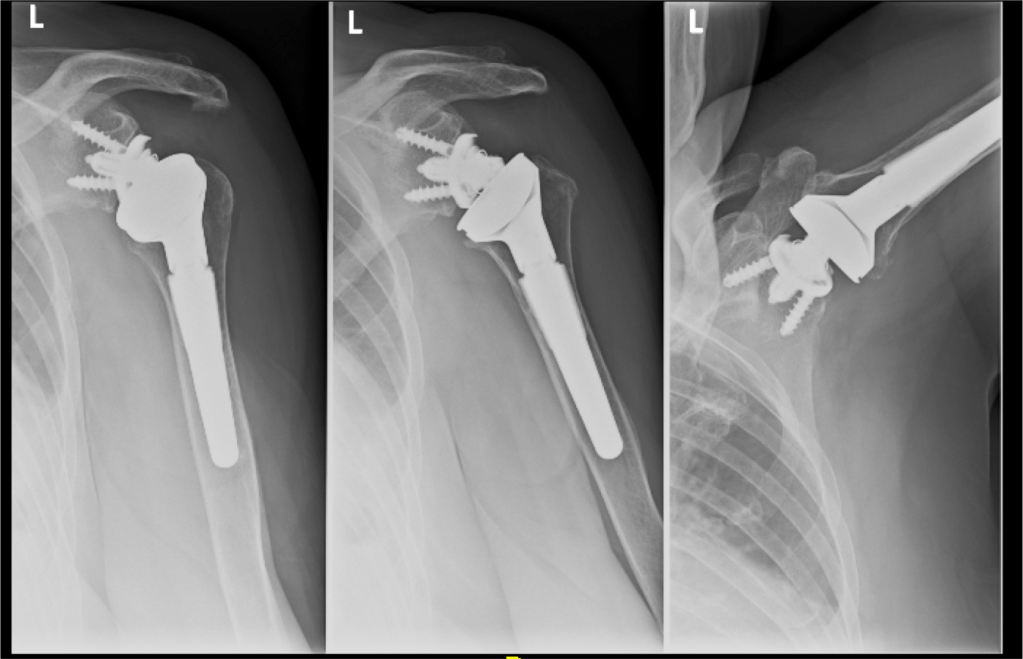

Patologie degenerative e protesi di spalla